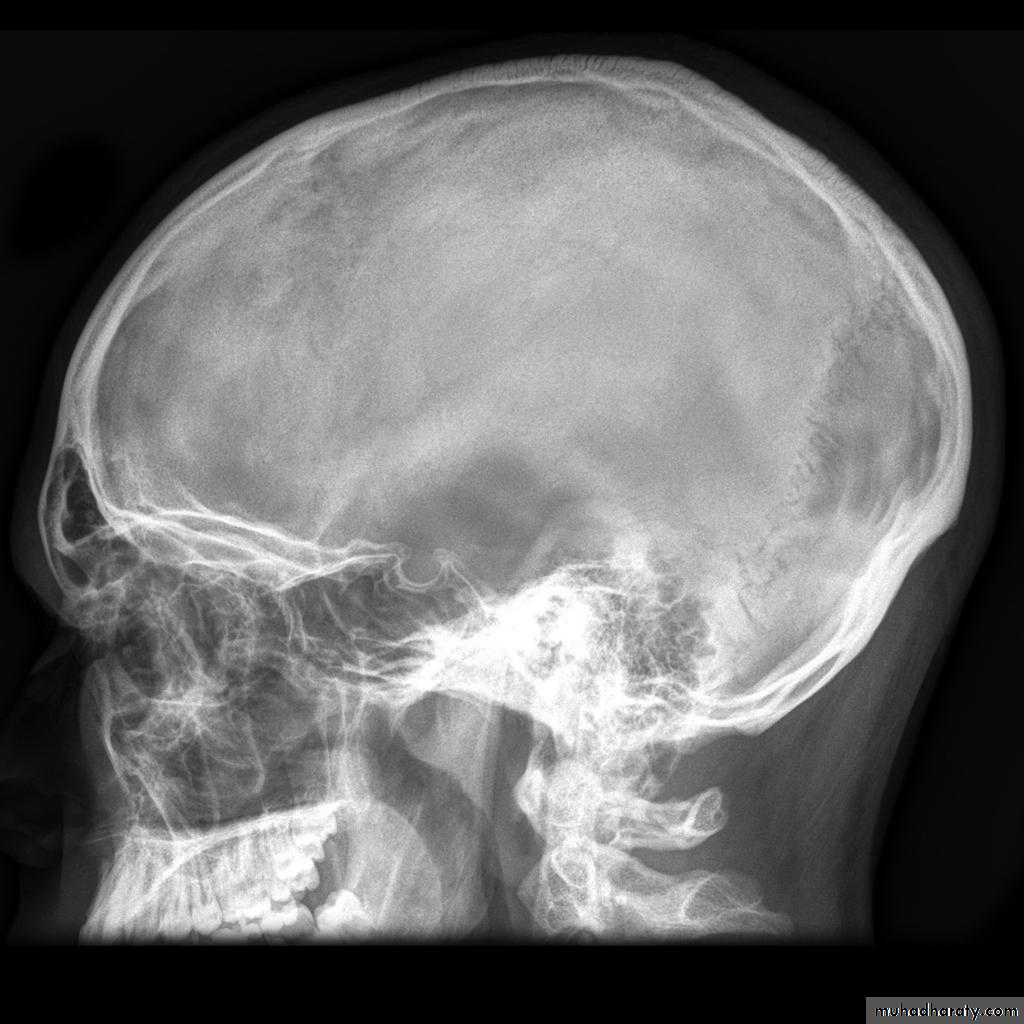

Skull X-rayBony configuration and shape

Bone densityAny Lytic lesion

Any fracture

Any calcification

Diploë, pituitary fossa, paranasal sinuses, orbits

The sutures

The normal pituitary fossa as shown in a lateral skull film can vary considerably in size. Normal figures are (length of 11-16 mm and a depth of 8-12 mm)